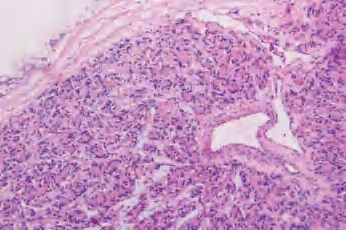

3.镜下 肿瘤细胞立方形、柱状或多角形,含一致深染的核。核分裂像罕见。继发病变包括间质水肿、纤维化、透明变性、出血、钙化,软骨化生、囊性变和梗死等(图3-31)。

图3-31 甲状腺滤泡性腺瘤